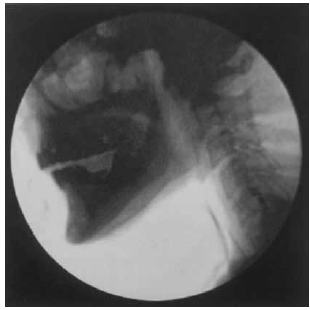

Segundo Magalhães e Magnoni (2022), nos pacientes oncológicos, principalmente com câncer de cabeça e pescoço, há modificações na anatomia e é importante conhecê-las para melhor avaliação.

Observe o exame a seguir:

(Magalhães e Magnoni: Disfagia orofaríngea no adulto em ambiente hospitalar. Rubio, 2022. p. 89)

O resultado do exame apresentado é compatível com um exemplo de